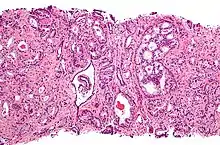

A diagnosis of prostate cancer requires a biopsy of the prostate be taken and examined under a microscope by a pathologist. Prostate biopsies are typically taken by a needle passing through the rectum or perineum, guided by transrectal ultrasound imaging, magnetic resonance imaging (MRI), or a combination of the two.[22][20] Ten to twelve samples are taken from several regions of the prostate to improve the chances of finding any tumors.[20] Biopsies are examined under a microscope by a pathologist, who determines the type and extent of cancerous cells present. Cancers are first classified based on their appearance under a microscope. Over 95% of prostate cancers are classified as adenocarcinomas (resembling gland tissue), with the rest largely squamous-cell carcinoma (resembling squamous cells, a type of epithelial cell) and transitional cell carcinoma (resembling transitional cells).[23]

Next tumor samples are graded based on how much the tumor tissue differs from normal prostate tissue; the more different the tumor appears, the faster the tumor is likely to grow. The Gleason grading system is commonly used, where the pathologist assigns a number from 1 (similar to prostate tissue) to 5 (least similar) for the most common pattern observed under the microscope, then does the same for the second-most common pattern. The sum of these two numbers is the Gleason score.[23] The total scores of 2 through 5 are no longer commonly used in practice, making the lowest score 6, and the highest score 10. Scores are commonly grouped into Gleason grade groups: a score of 6 or lower is Gleason grade group 1; a score of 7 with the first number (from the most common pattern) 3 and the second number 4 is grade group 2; the reverse – first number 4, second number 3 – is grade group 3; a score of 8 is grade group 4; a score of 9 or 10 is grade group 5.[23] Higher Gleason scores and higher grade groups represent cancer cases likely to be more aggressive with worse prognosis.[23]